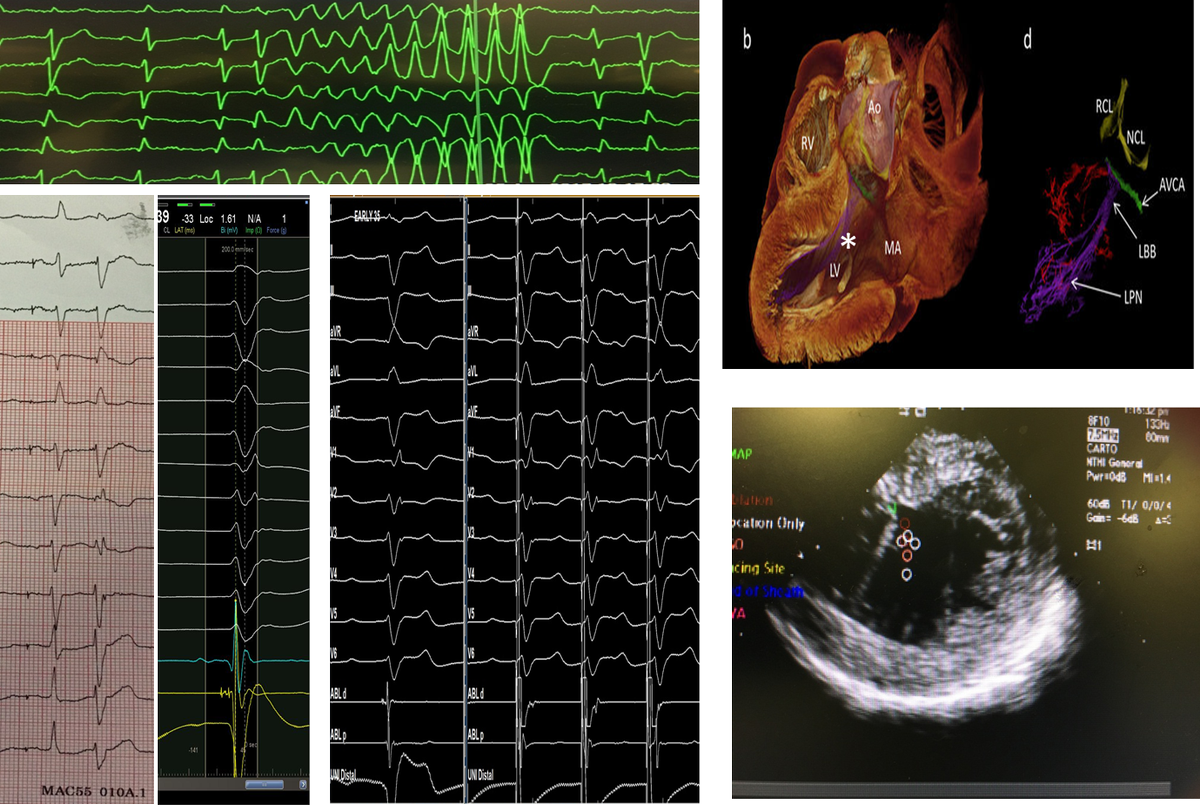

65 yo with symptomatic multifocal PVCs, ~30K, EF 45%,  3 different PVCs were ablated today..fun & require patience, thanks to the team!